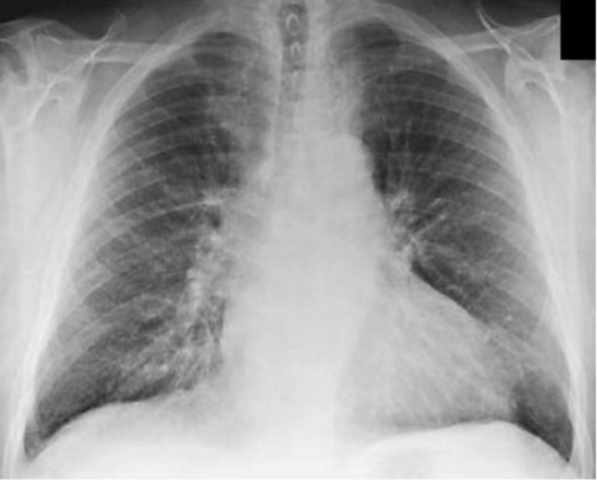

Se realizaron los paraclínicos: Radiografía de tórax muestra cardiomegalia moderada con aumento de la trama vascular pulmonar y opacidad de las bases pulmonares inferiores. Ecografía abdominal muestra un tamaño adecuado de riñón de ambos riñones sin evidencia de dilatación pielocalicial. El ecocardiograma revela una moderada cantidad de líquido alrededor del corazón; por lo que se decide realizar una pericardiocentesis, obteniéndose 250 cc de líquido hemático.